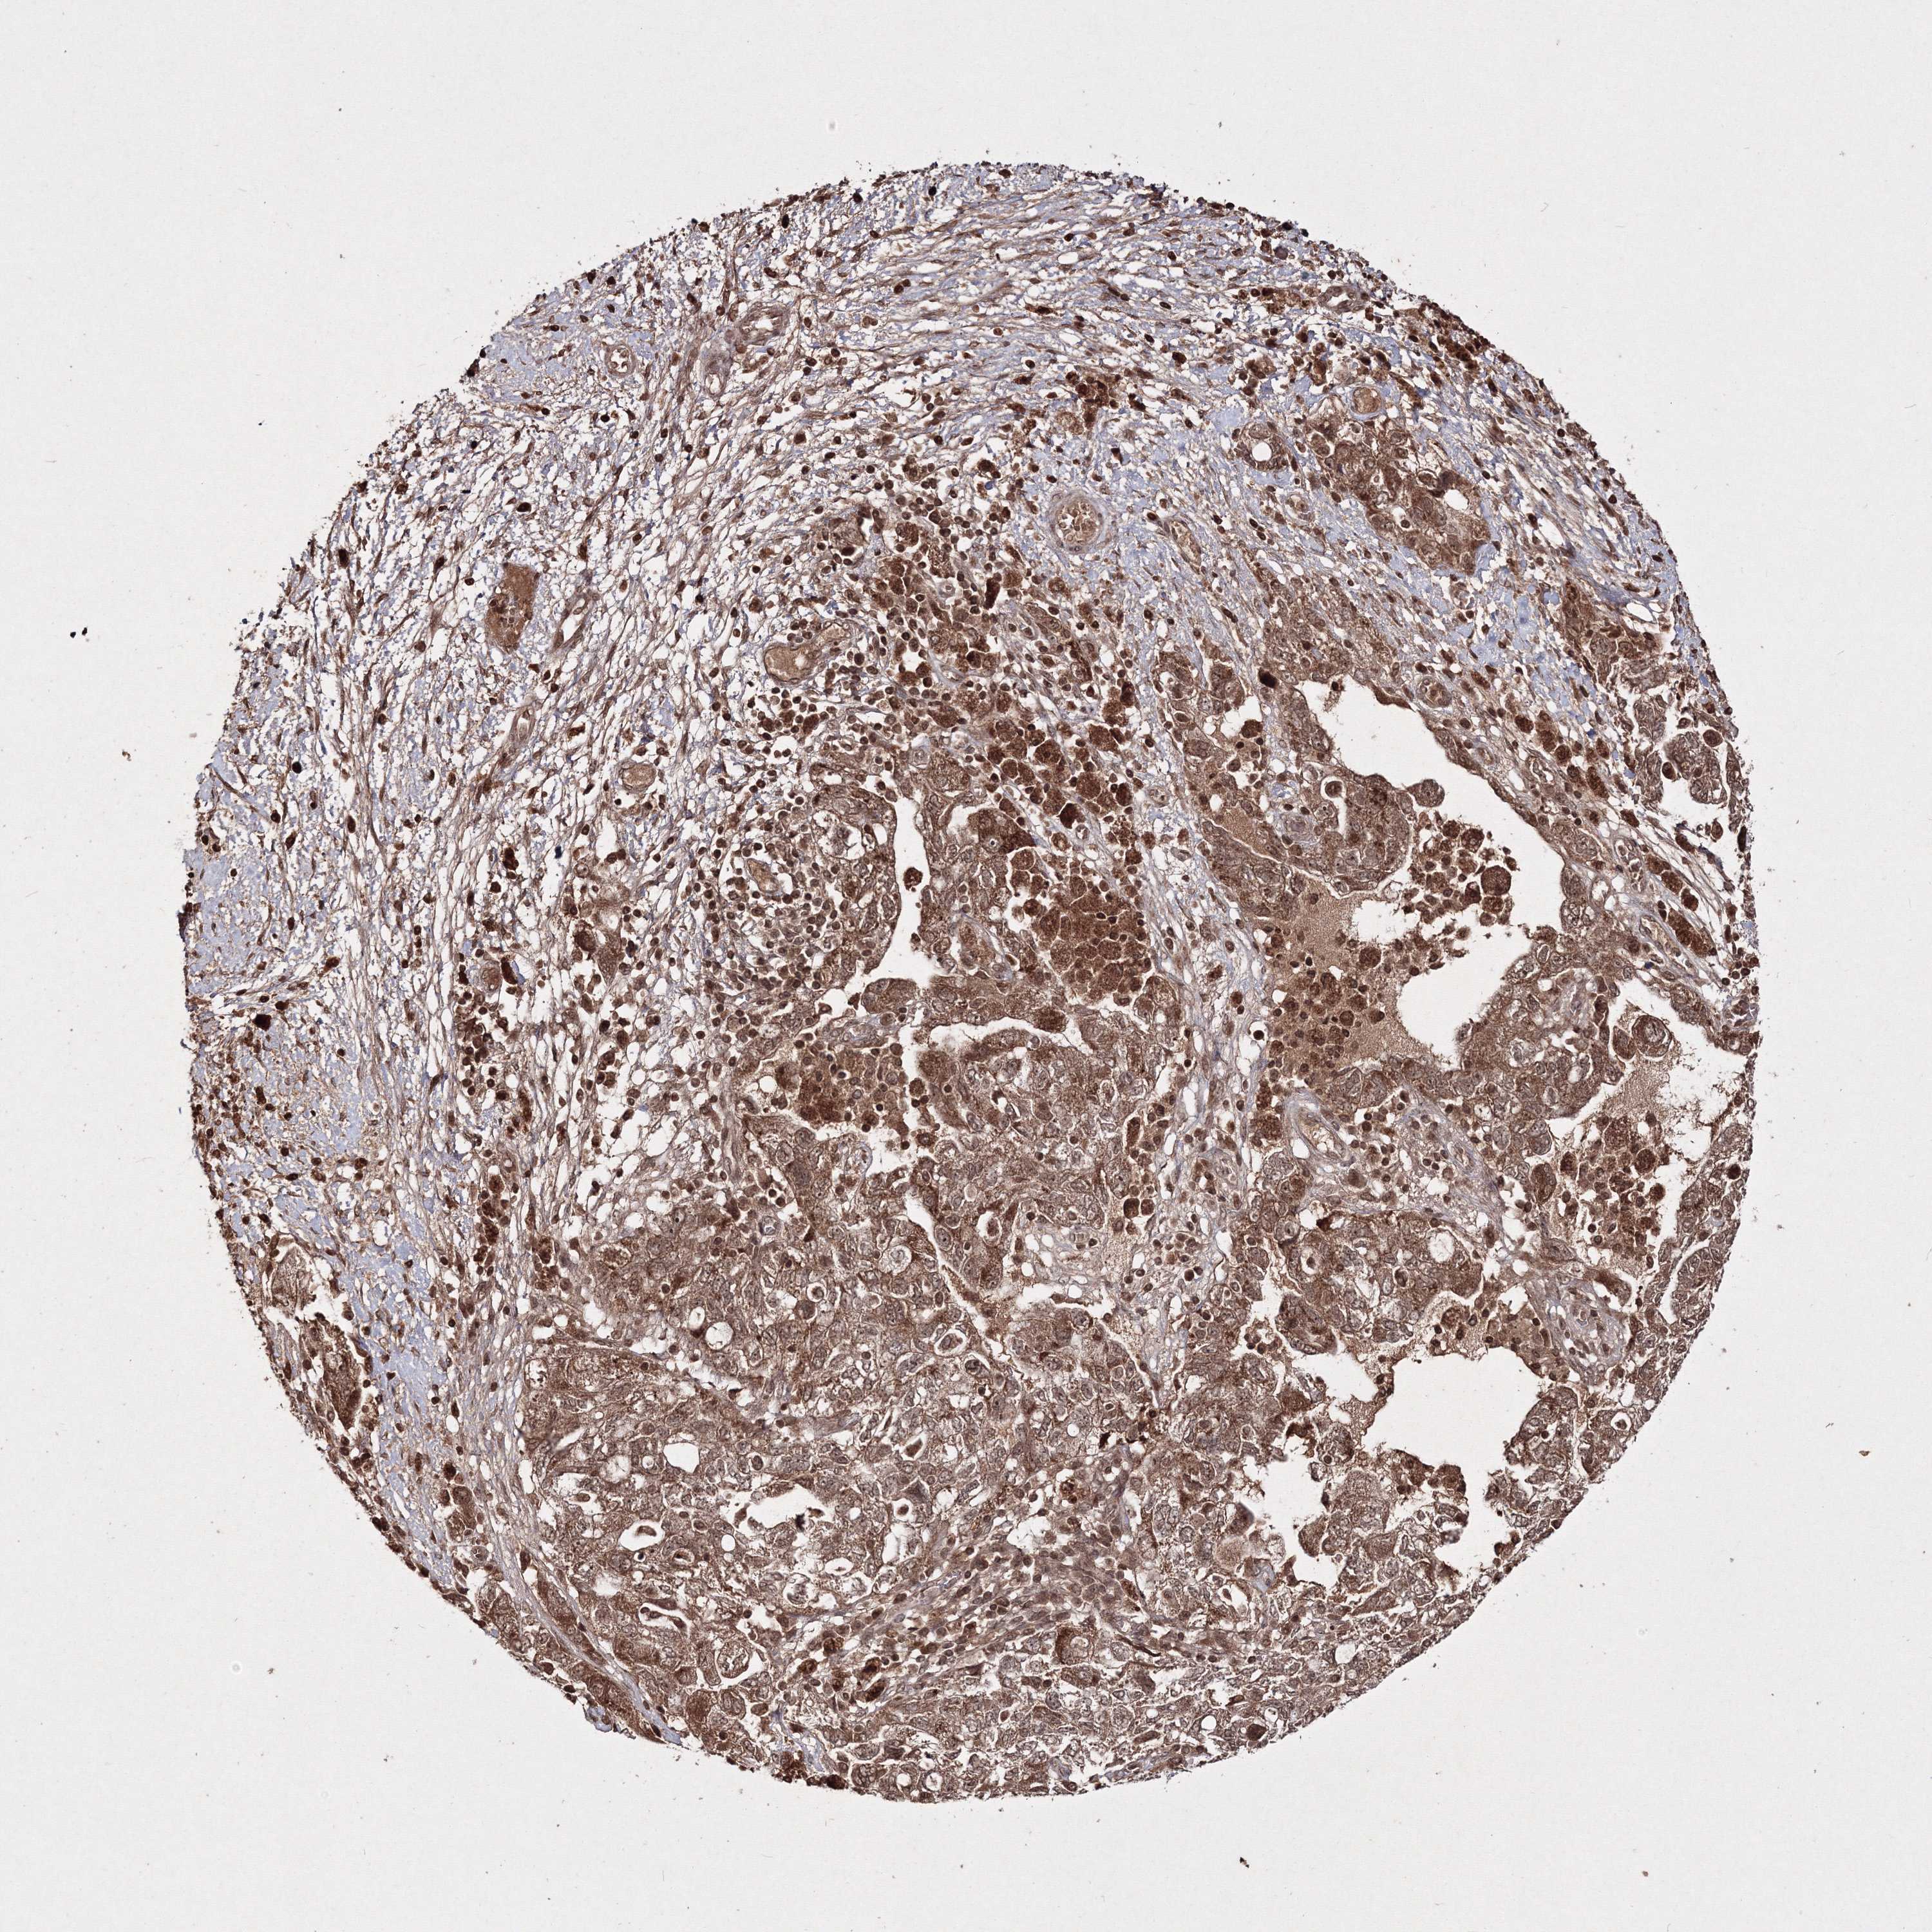

OVARIAN CANCER - Protein expressioni

A mouse-over function shows sample information and annotation data. Click on an image to view it in a full screen mode. Samples can be filtered based on level of antibody staining by selecting one or several of the following categories: high, medium, low and not detected. The assay and annotation is described here.

Note that samples used for immunohistochemistry by the Human Protein Atlas do not correspond to samples in the TCGA dataset.

Antibody stainingi

Antibody staining in the annotated cell types in the current human tissue is reported as not detected, low, medium, or high, based on conventional immunohistochemistry profiling in selected tissues. This score is based on the combination of the staining intensity and fraction of stained cells.

Each image is clickable and will lead to virtual microscopy that enables deeper exploration of all samples and also displays staining intensity scores, fraction scores and subcellular localization as well as patient and tissue information for each sample.

Antibody HPA032141

Antibody HPA032142

Antibody CAB032689

Staining

High

Medium

Low

Not detected

Intensity

Strong

Moderate

Weak

Negative

Quantity

>75%

75%-25%

<25%

None

Location

Nuclear

Cytoplasmic/membranous

Cytoplasmic/membranous,nuclear

Cystadenocarcinoma, serous, NOS

Carcinoma, endometroid

Cystadenocarcinoma, mucinous, NOS

Carcinoma, NOS